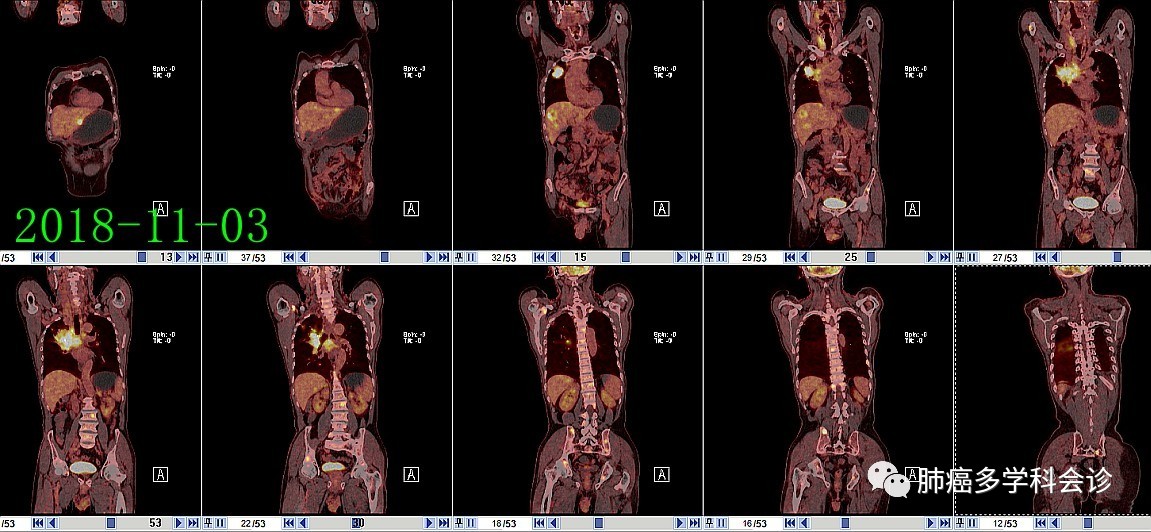

PET CT图像显示肿瘤转移的部位:

3.jpg2018-11-06开始“依托泊苷+铂”化疗2周期,之后拒绝进一步治疗。